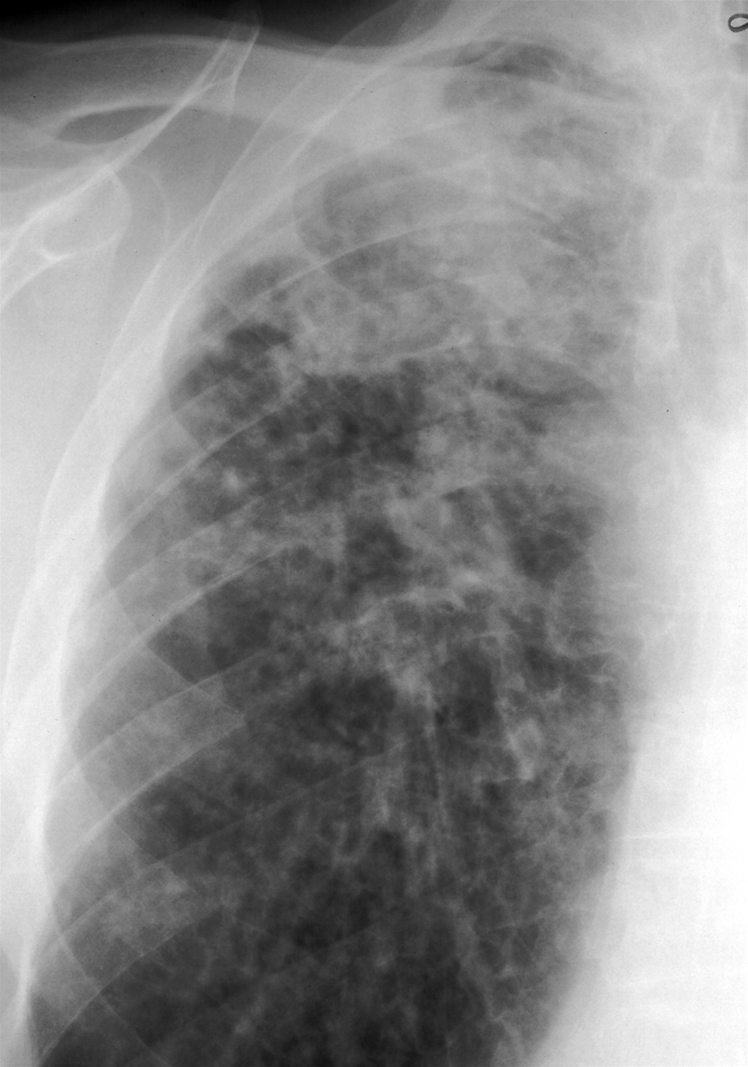

Røntgenbilledet viser den øverste del af højre lunge.

Der reticulære (stribeformede) og nodulære (runde) fortætninger i overlappen.

Sådanne forandringer kan ud over ved silikose også ses ved andre typer af lungesygdom.